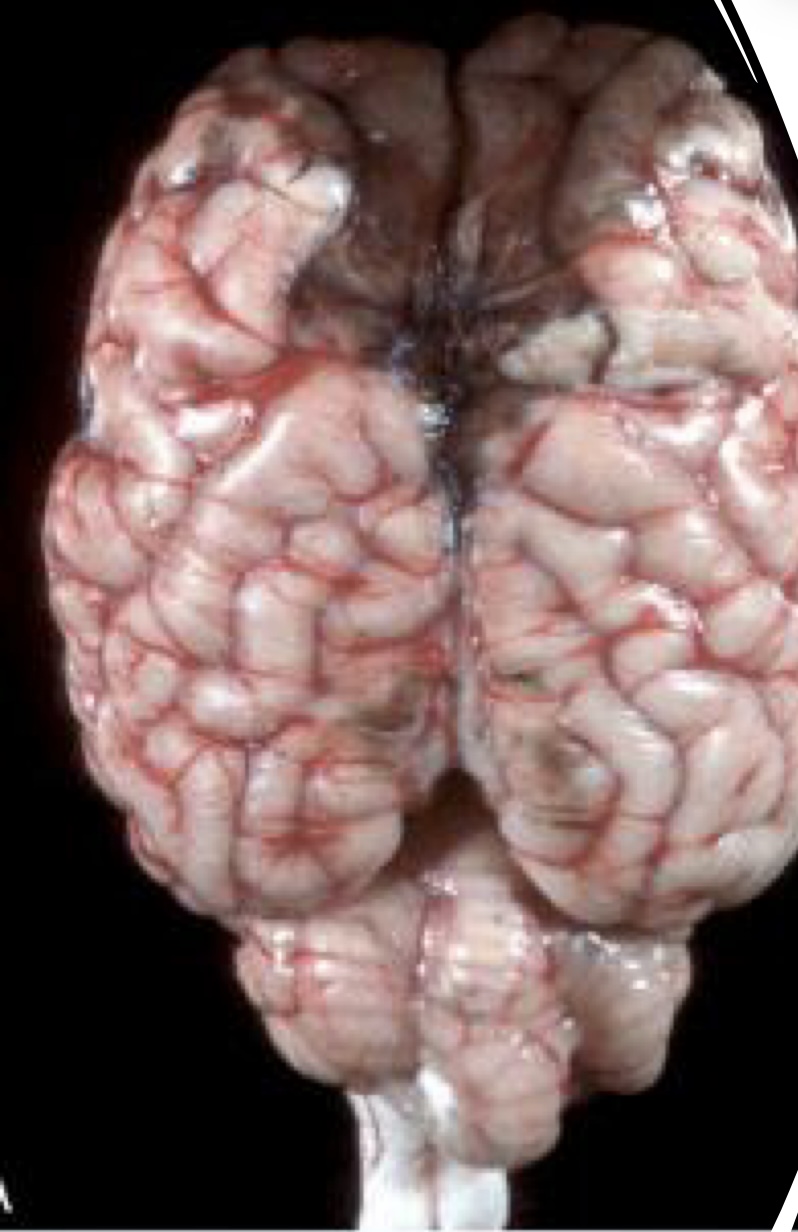

what is this?

metastatic hemangiosarcoma → prominent hematogenous metastases, which appear as black nodules of various sizes distributed throughout the brain

in an unfixed specimen, what color would the nodules of metastatic hemangiosarcoma be?

red to dark red